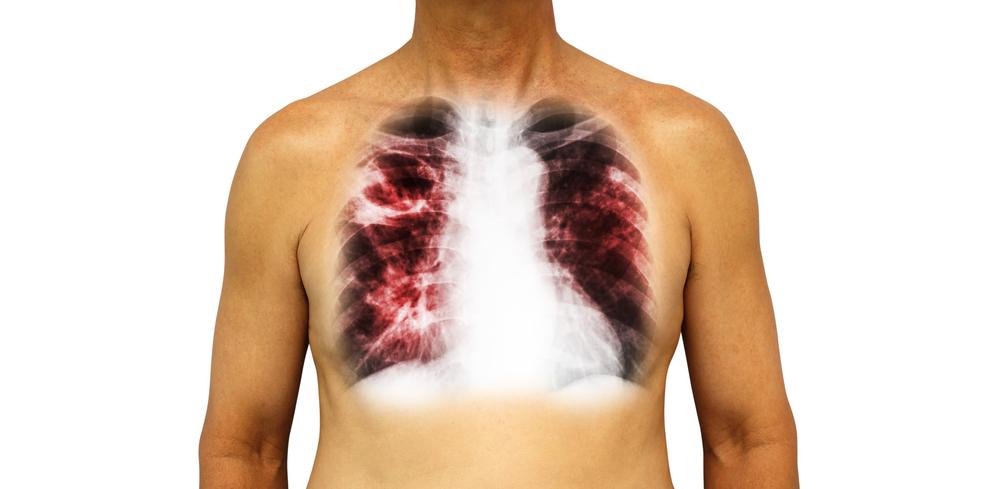

Sau đó, bác sĩ sẽ chỉ định thực hiện các kỹ thuật cận lâm sàng như xét nghiệm chức năng phổi, chụp X-quang ngực, siêu âm tim, chụp cắt lớp vi tính, xét nghiệm bệnh tự miễn, xét nghiệm vi sinh, xét nghiệm máu, nội soi phế quản, sinh thiết phổi để tìm ra nguyên nhân và chẩn đoán chính xác nhất.